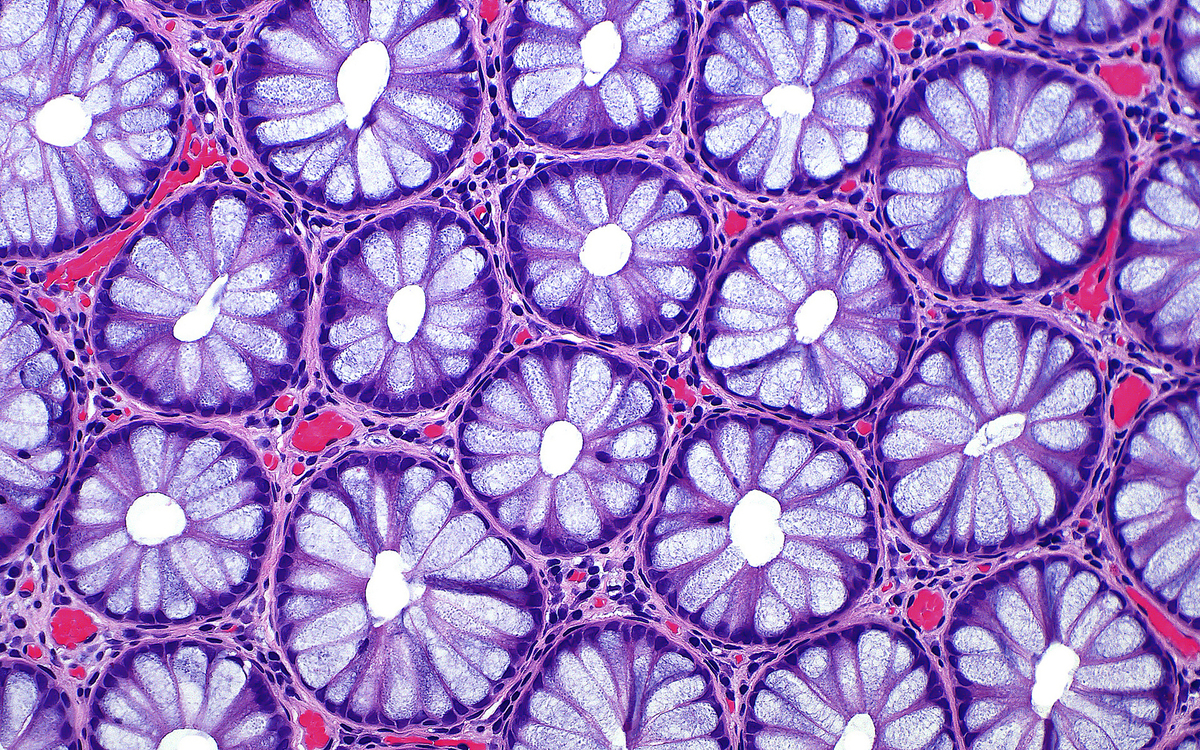

10. Ανθρώπινες επιθηλιακές κρύπτες του παχέος εντέρου

Η παραπάνω φωτογραφία με τα εντυπωσιακά χρώματα κέρδισε τη 15η θέση στον διαγωνισμό. Ο Δρ. Ziad El-Zaatari απεικονίζει τις διατομές φυσιολογικών ανθρώπινων επιθηλιακών κρυπτών του παχέος εντέρου.